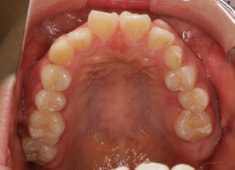

治療前

治療開始時